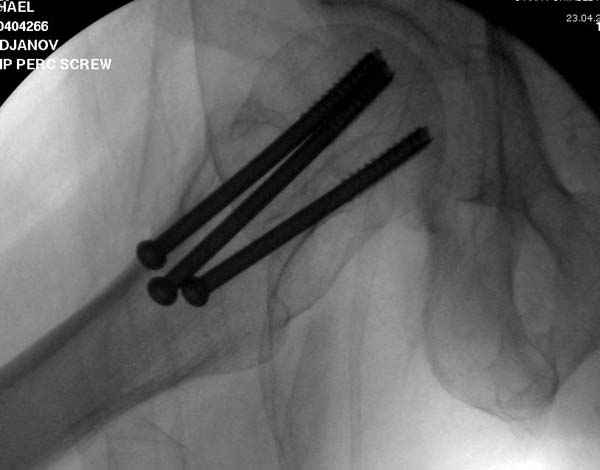

Re: неполный перелом шейки

“А что означает профилактическая перкутанная фиксация? Профилактика чего? Резорбции что ли? Снимки у Вас высокого качества- это ясно, а ППФ - это не ясно.”

Профилактику дальнейшего раскола неполного перелома шейки провели тремя канюлированными шурупами.

На второй день после выписки упал дома. Снимки приложены. Коллеги рекомендуют удаление шурупа и вытяжение. Что делать?